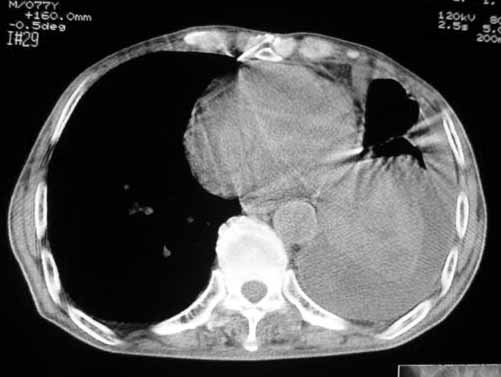

以下是引用luochengyi在2007-5-24 14:33:00的发言:[br]考虑左下肺癌。左侧胸腔积液。

以下是引用adams在2007-5-24 17:12:00的发言:[br]支持“考虑左下肺癌,左侧胸腔积液,建议胸水检查”。[br] [br]

以下是引用fumaogui在2007-5-24 16:20:00的发言:[br]左侧胸腔积液.[br]左下叶不张考虑中心型肺癌[br]建议纤支镜检查.